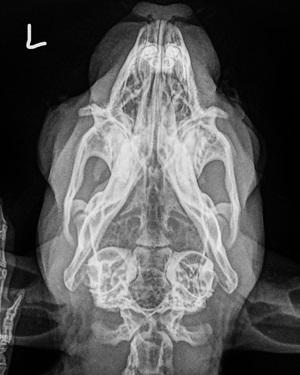

Am wichtigsten bei der Röntgenuntersuchung ist die dorsoventrale Aufnahme, d. h. das Kaninchen sitzt bzw. liegt gerade auf dem Bauch und der Schädel wird "von oben nach unten" geröngt. Auf die Weise können beide Mittel- und Innenohren nicht nur separat, sondern auch im Seitenvergleich beurteilt werden.

Wichtig ist eine absolut gerade Lagerung, da verkippte Aufnahmen Asymmetrien vortäuschen können. Hierfür hat es sich bewährt, das Kaninchen auf den Röntgentisch zu setzen, anschließend eine Mullbinde o. ä. über seinen Kopf zu spannen und den Kopf damit nach unten zu drücken, sodass das Kinn zwischen den Vorderbeinen auf dem Tisch zu liegen kommt. Die meisten Kaninchen tolerieren diese Lagerung völlig problemlos.

Mithilfe der Aufnahme kann insbesondere festgestellt werden, ob die normalerweise gut belüfteten Bullae tympanicae (Paukenhöhlenblasen) mit Sekret gefüllt, ihre Wände entzündlich verdickt oder Knochenauflösungen vorhanden sind.

Die Röntgendiagnostik liefert einen ersten Anhaltspunkt dafür, ob eine Oittis media / interna vorliegt. Eine Narkose ist hierfür nicht nötig und v. a. bei bereits geschwächten Tieren nicht zu empfehlen.

Gerade im Anfangsstadium einer Infektion ist es allerdings möglich, dass Veränderungen auf Röntgenbildern noch nicht sichtbar sind. Selbst bei Kaninchen, die bereits hochgradige neurologische Symptome zeigen, können die Mittelohren röntgenologisch noch unauffällig wirken - während sie im CT bereits deutlich sichtbar mit Sekret gefüllt sind.